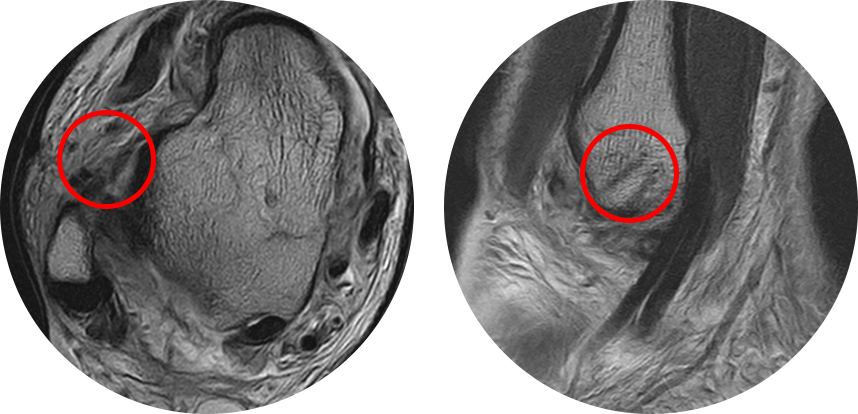

수술을 할 정도의 심한 인대 손상이 있는 경우 발목 연골 손상 등이 동반되는 경우가 쉬운데, MRI에서 놓치기 쉽고

경비인대 손상 중 일부는 관절경 하에서만 발견되는 경우도 흔하기 때문에 진단적인 목적으로 시행합니다.

3도 손상의 경우 전거비인대 완전 파열 뿐만 아니라 종비인대의 손상도 흔히 같이 동반되어 있기 때문에

최소 절개를 통해 micro MBO 수술법을 이용하여 단단하게 인대를 봉합하여 재파열의 가능성을 최소로 낮춥니다.

수술 전 MRI 에서 전거비인대 및 종비인대의 완전 파열 소견을 보이며 관절내에 피가 고여 있는 모습이 관찰됩니다.